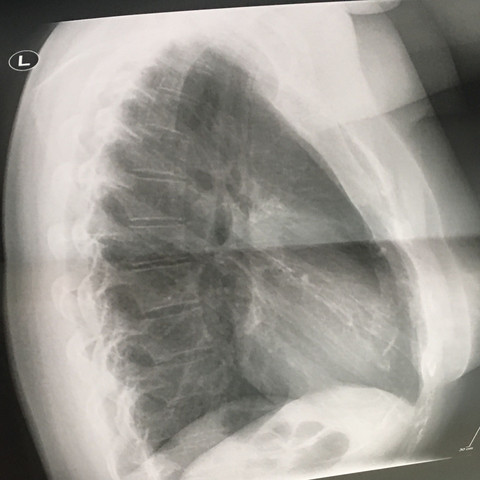

Brustkorb